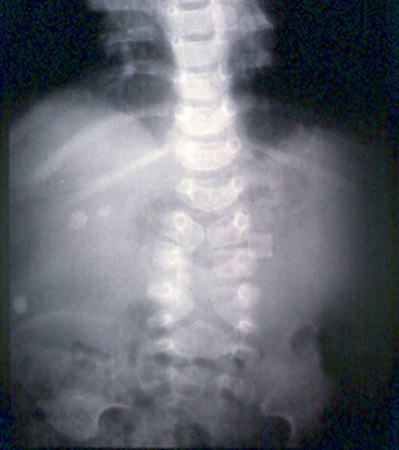

- radiografia abdominal:

alças do intestino delgado dilatadas, níveis hidroaéreos em todo o abdome

Mais - radiografia abdominal:

obstrução parcial ou completa; alças intestinais dilatadas; níveis hidroaéreos; ar livre abdominal com perfuração

distensão gasosa do intestino grosso; volvo sugerido por alça intestinal em forma de feijão

alças do intestino dilatadas, pneumatose intestinal, gás na veia porta, ar livre, alça intestinal presa; ausência do padrão de gases normal no intestino